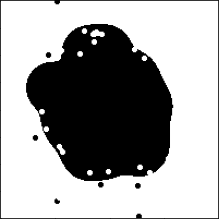

4.2 Application to GBM MRI Images

GBM is the most common malignant grade IV brain tumor (Surawicz et al., 1999). GBM is distinguished from lower-grade astrocytomas (grades II and III) by its accelerated growth rate. The rapid outward growth of GBM develops necrosis, which is considered a hallmark of GBM. On T1-weighted contrast-enhanced imaging MRI, most GBM cases show a ring-shaped enhancement made of hypervascular tissues with a necrotic region at the center (Zhu et al., 2000; Henson, Gaviani and Gonzalez, 2005). Figure 8(a) shows the MRI image of the GBM patient with a ring-enhancing mass. The presence of necrosis is a significant prognosis factor (Nelson et al., 1983), and clinical studies show that the degree of necrosis is negatively associated with a survival rate (Hammoud et al., 1996; Raza et al., 2002). However, due to its irregular shape, multifocal enhancement, and the existence of multiple small lesions, evaluation of GBM shapes using MRI images could be difficult (Eisenhauer et al., 2009; Upadhyay and Waldman, 2011).

We use 77 GBM patients’ MRI scans obtained from The Cancer Imaging Archive (TCIA) (Scarpace et al., 2016) and their clinical data retrieved from The Cancer Genome Atlas (TCGA) (Network et al., 2008). The MRI images are segmented into two classes of the tumor and non-tumor regions using the Medical Imaging Interaction Toolkit with augmented tools for segmentation (Chen and Rabadán, 2017). Each patient has approximately 23 to 25 segmented MRI images and the spaces between the MRI images are not the same. The size of images is either or . We only use 1,190 MRI images that have more than 100 tumor pixels because some images do not include tumor regions that are not large enough. The segmented binary images are transformed by the SEDT-2. We note that 2D MRI images are used because the vertical spaces between the MRI images are not the same. However, our method can easily be extended to 3D images. Figures 8(b) and 8(c) show the segmented binary image and distance transformed by the SEDT-2.

The topological shape features in the MRI images are obtained by computing persistent homology of the cubical complex based on the SEDT-2 values. Especially the ring-shaped enhancements of the GBM patients’ MRI images are recorded as dimension-one topological shape features. As illustrated in Figure 2(b), the broken-ring- and unbroken-ring-shaped masses appear in quadrant I and II of the dimension-one persistence diagram, respectively.

For the GBM images, the number of topological shape features is much smaller than that of the lung cancer pathology images. The median of the number of computed persistent homology features per image slice is 16 for dimension-zero and 17 for dimension-one, respectively. This is because MRI images are scanned in lower resolution than pathology images, and GBM tumors are smaller and simpler than lung cancer regions. Also, the persistent homology features obtained from the images of size 512512 are divided by two for a consistent comparison with the images of size 256256. The ranges of persistent homology shape summaries are for dimension-zero and for dimension-one. We represent the topological shape features as persistence surface functions using the smoothing parameters and . The mean persistence surface function is used to represent each patient’s tumor shape information.

Table 2 summarizes the results of the CoxPH, FCoxPH-SECT, and FCoxPH models. Age has small p-values in all models. The p-values of the Wald tests are , , and for the CoxPH, FCoxPH-SECT, and FCoxPH models, respectively.

Figure 9 presents the estimated coefficient of dimension-one persistence surface function of the GBM patients. The blue-colored areas indicate that a larger number of small- and large-sized broken-ring-shaped features are associated with higher risks. These patterns are most likely to correspond to the large necrotic center and heterogeneous enhancement outside of the rim.